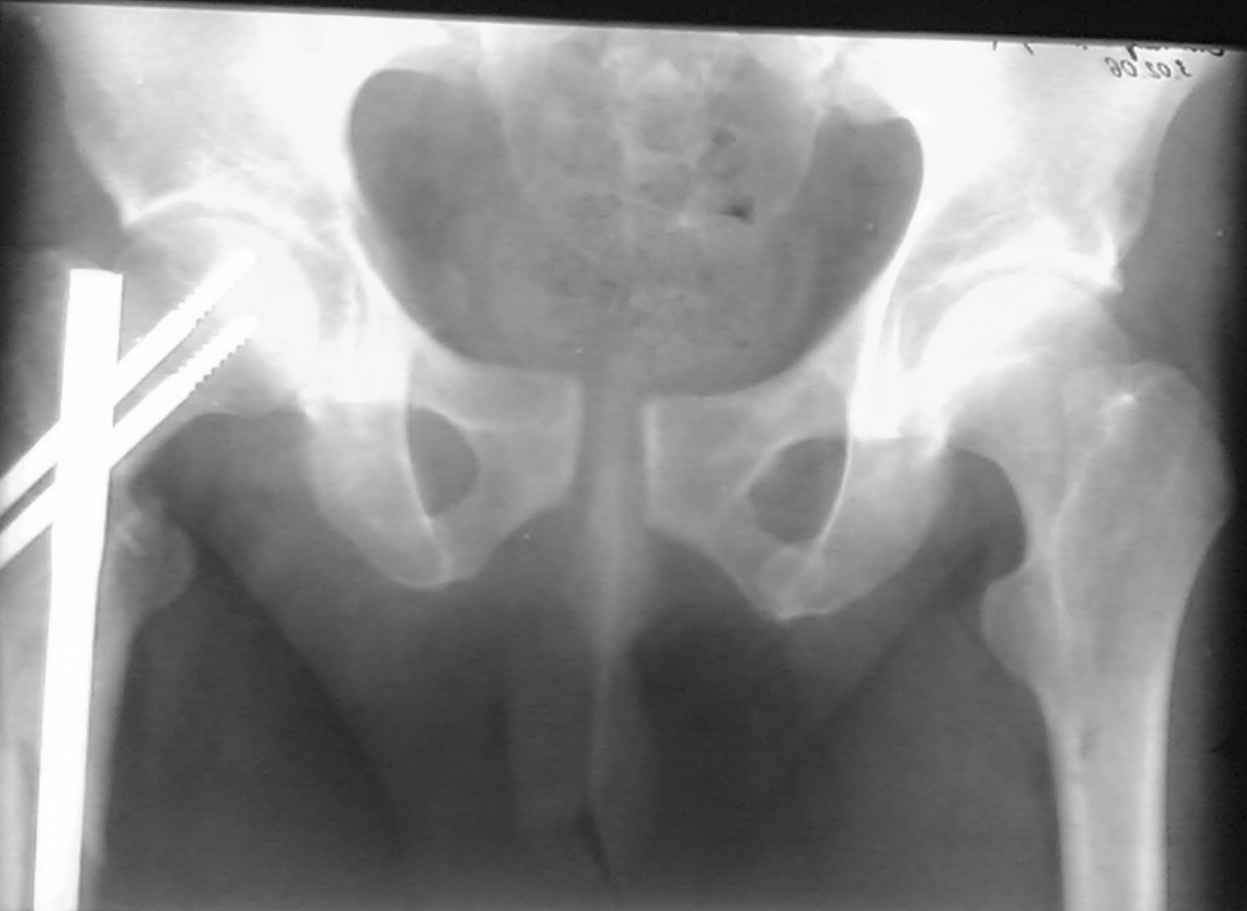

ПЕРЕСМАТРИВАЛ РАЗНЫЕ СНИМКИ И НАШЕЛ НА ЭТУ ТЕМУ ФОРУМА СНИМОК. БОЛЬНОЙ БЫЛ ПРООПЕРИРОВАН НА ПРАВОЕ БЕДРО ПОСЛЕ ЧЕГО СДЕЛАН ТАЗ В ЦЕЛОМ. ВОТ ЧТО НАШЛОСЬ.

КАКОЕ ВАШЕ МНЕНИЕ О ТАКТИКЕ.

ДУМАЮ ПРОШЛО ОКОЛО 10 ДНЕЙ.

Другими словами, необходимо принимать во внимание механизм травмы, и то, что диастаз более 2.5 см это уже показание к операции. Дисатаз менее 2,5 см на плоскостных рентегограммах в одной проекции, еще ничего не значит: не значит, что все хорошо сзади.

В представленном случае повреждение несомненно ротационное и реальный диастаз как раз около пограничных 2,5 см, репозиция идеальная,

достигнута в первые дни после травмы. Я бы ограничился 3 мес фиксации в

аппарате с ограничением нагрузки первый месяц, и функциональными снимками в 6 -8 недель.